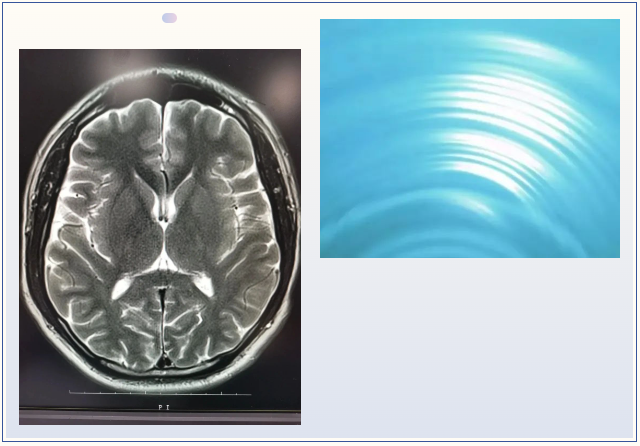

核磁共振 摇一摇再看

核磁共振机使用较强大的磁场,使人体中所有水分子磁场的磁力线方向一致,这时磁共振机的磁场突然消失,身体中水分子的磁力线方向,突然恢复到原来随意排列的状态。简单说就相当于用手摇一摇,让水分子振动起来,再平静下来,找出有问题的振动。所以,核磁共振(MRI)也被戏说为是摇摇看的检查。

颈椎病、腰椎间盘突出等椎间盘疾病需要观察椎间盘与相应的神经根,要想更好观察这些软组织,最优选择就是核磁。同样,对于大脑、四肢关节、肌肉、脂肪组织检查,核磁也是首选。